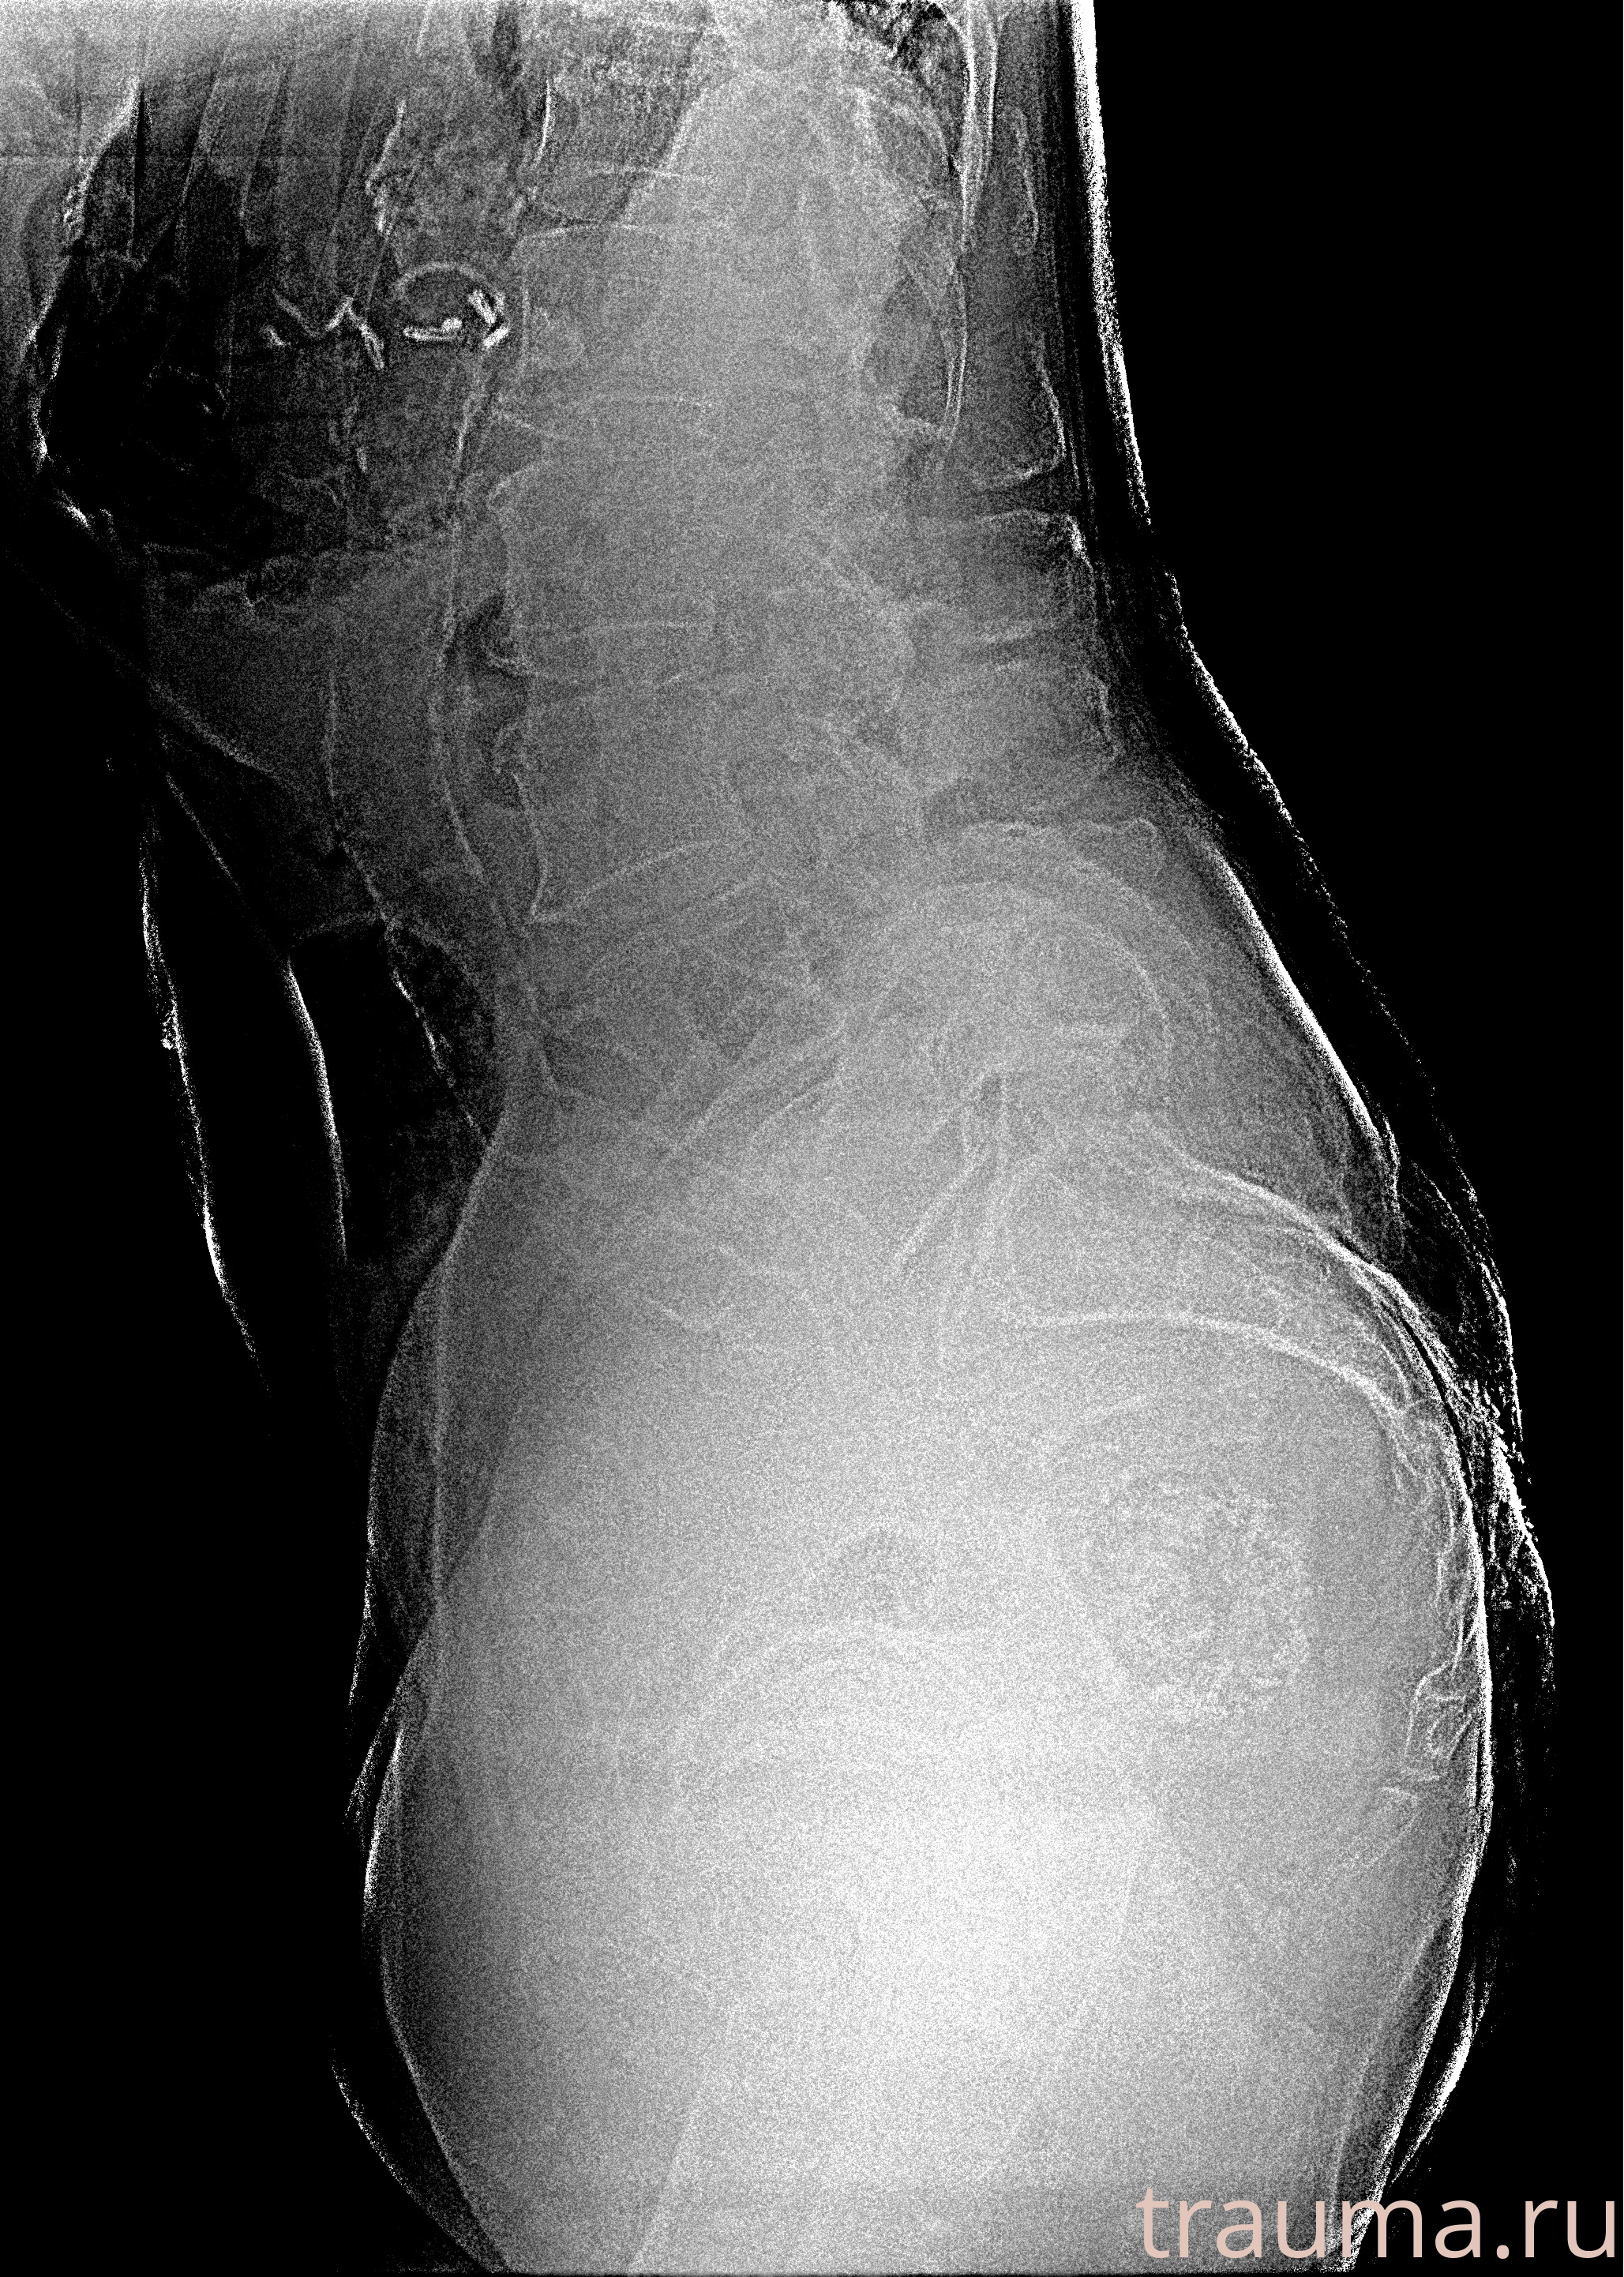

Рентгенограммы

Рентген на дому: по вашему адресу приезжает врач-рентгенолог, травматолог-ортопед с мобильным рентгеновским аппаратом, проводит диагностику травмы или заболевания, делает необходимые рентгенограммы, дает рекомендации по дальнейшему лечению. Получить качественные снимки в домашних условиях возможно благодаря уникальной методике, разработанной МосРентген Центром для института  Склифосовского

Яркость: 1   Контраст: 1   Инвертировать: 0 Увеличение: 1

Перетаскивайте мышь вверх/вниз для контраста, влево/право для яркости. Прокрутка колесом изменяет масштаб. Нажмите Сбросить для возврата к исходному изображению. При увеличении держите мышь в той области, которую хотите рассмотреть.